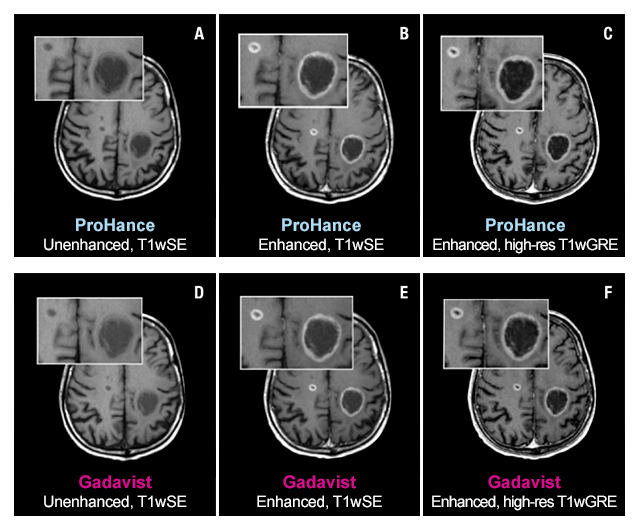

Case Study 1

61-year-old male with brain metastases from primary lung cancer. Two lesions clearly seen in both exams show no differences in contrast enhancement or in the morphology of lesions.1

The TRUTH study results demonstrate no differences in contrast enhancement of lesion morphology.1

The 95% confidence intervals for all qualitative assessments confirm that ProHance is not inferior to Gadavist.1

No significant differences noted by any reader for any parameter:1

- Global Diagnostic Preference

- Lesion Border Delineation

- Lesion Internal Morphology

- Lesion Qualitative Contrast Enhancement

- Lesion Extent